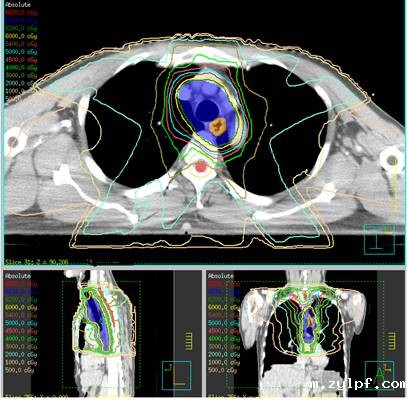

我科常见病种的靶区计划图:

肺癌SBRT